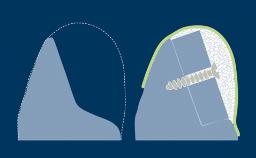

The periosteal releasing incision, or PRI, is a common oral surgical technique that is undertaken to increase the mobility of a surgical flap.

When performed correctly, the periosteal releasing incision allows the flap to be coronally advanced so that tension-free primary closure of the surgical site can be achieved.

- outline the steps in performing a PRI